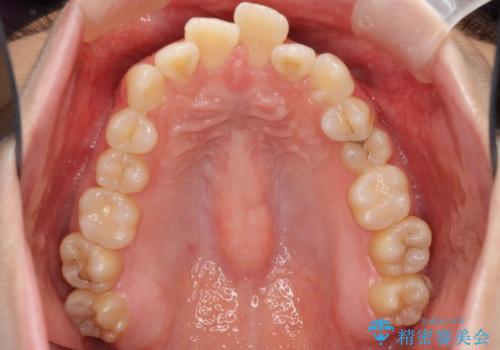

左上の小臼歯が込み合っており、虫歯治療が厳しい状態でした。

矯正治療をおすすめし、ちょうど虫歯がひどい歯は抜歯して前歯を下げました。